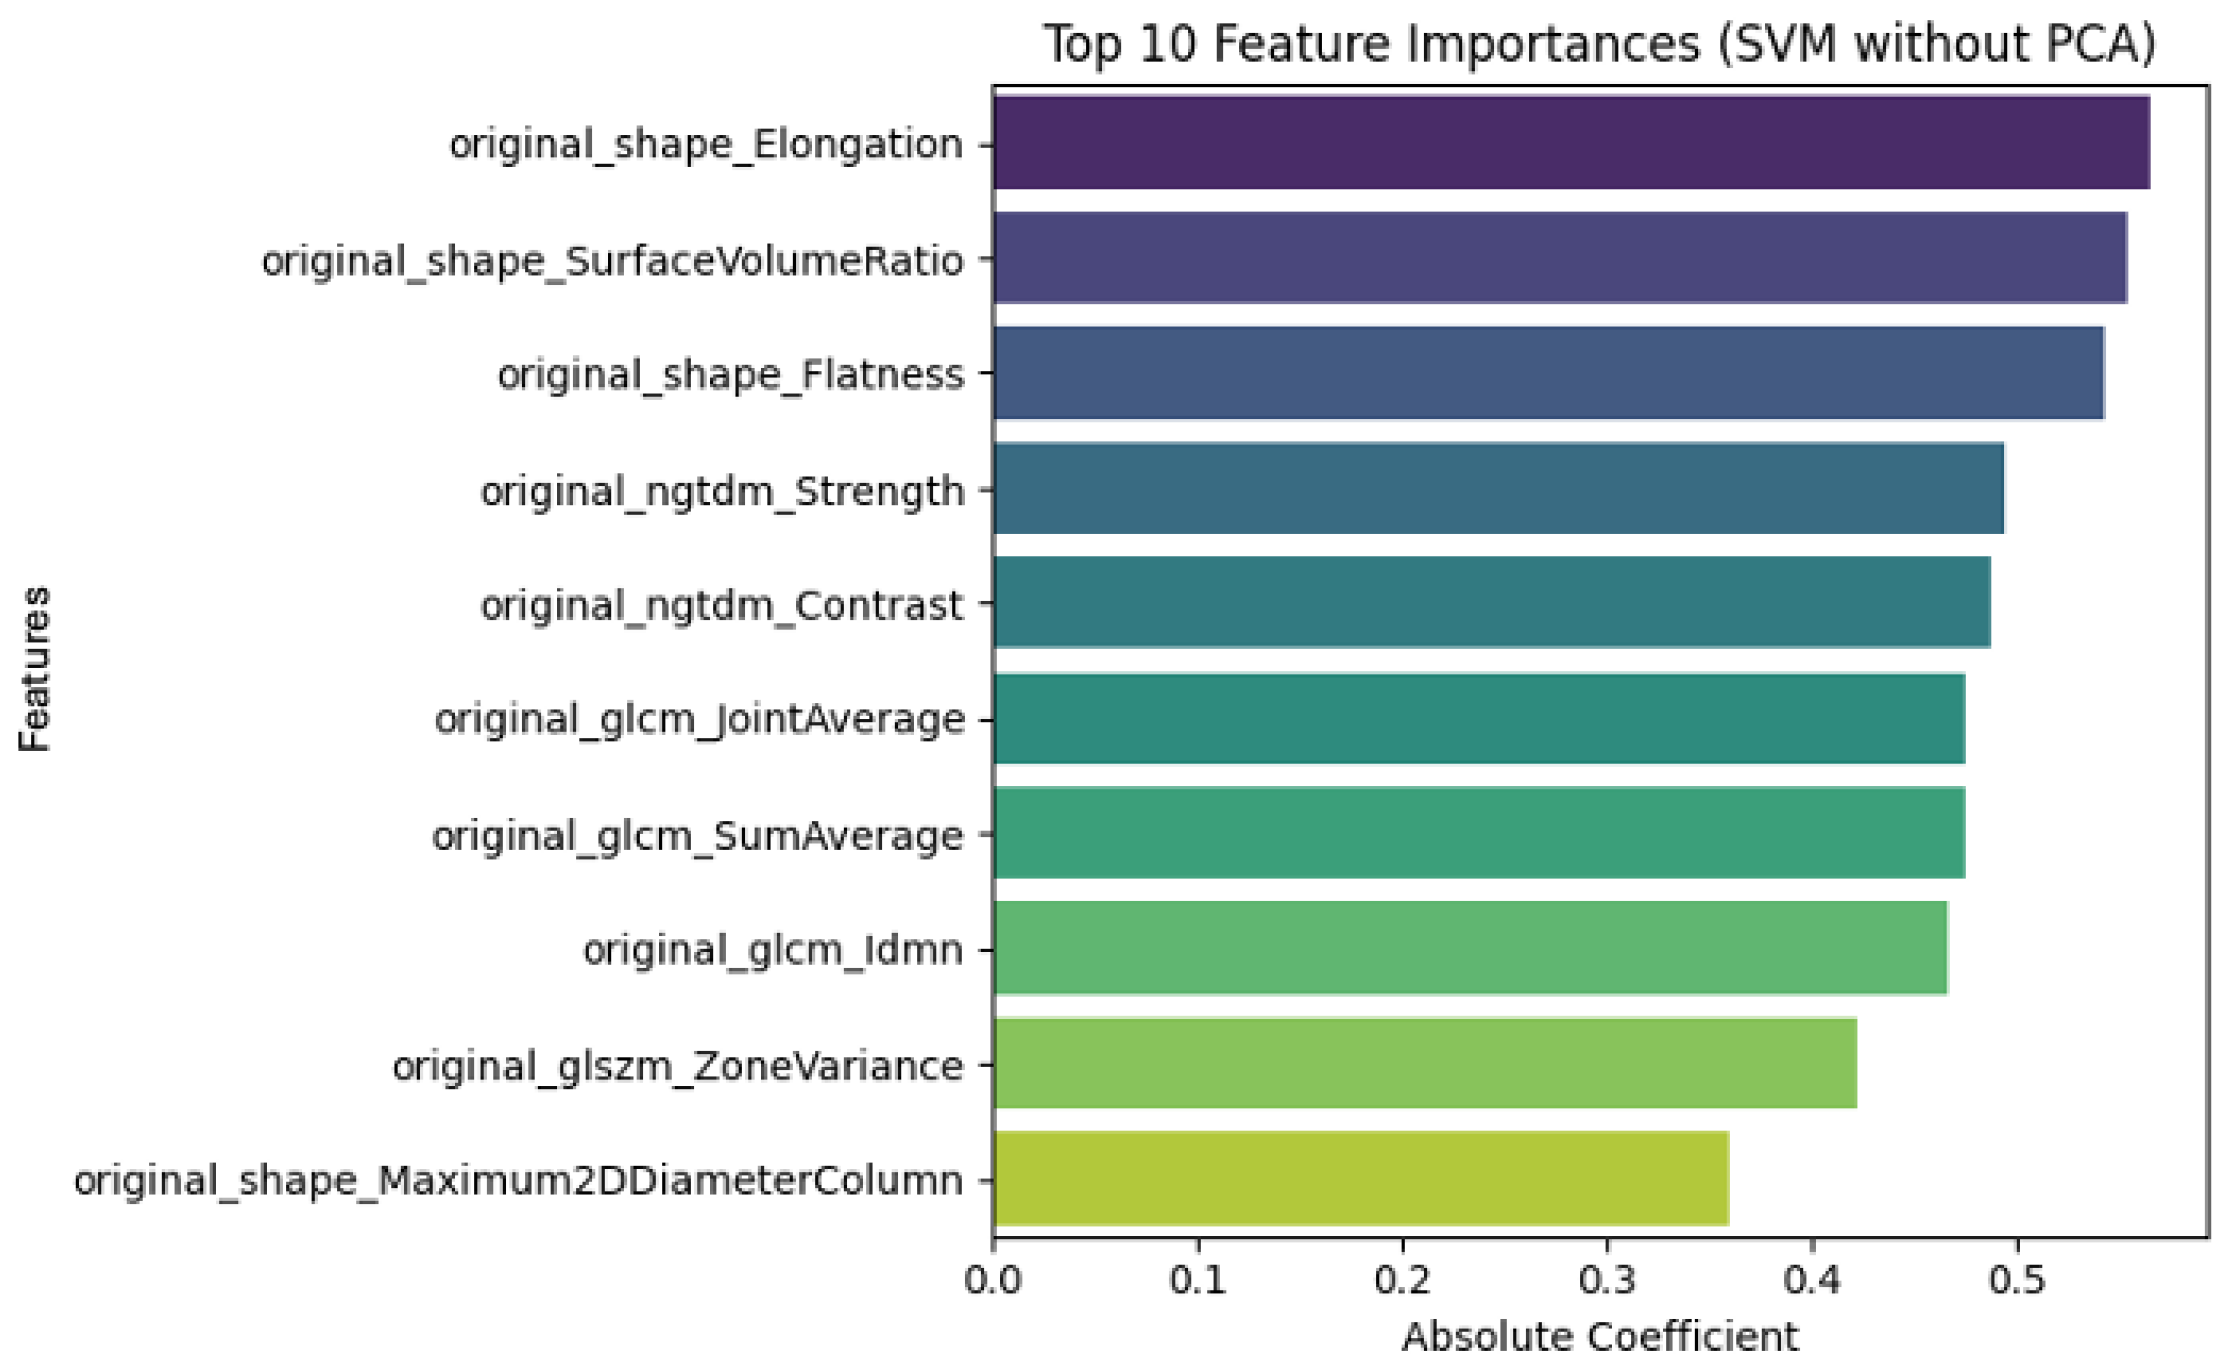

3.2. Radiomic Feature Interpretability and Clinical Relevance

| Feature | Interpretation |

|---|---|

| Shape Features | |

| original_shape_Elongation | Measures how stretched the tumor is. A value close to 1 indicates a rounder shape; lower values indicate elongation. |

| original_shape_Flatness | Describes the flatness of the shape by assessing the ratio of the minor to major principal components. |

| original_shape_Maximum 2DDiameterColumn | Maximum 2D diameter of the lesion measured along the column direction. Useful for assessing size in a planar view. |

| Texture Features (GLCM) | |

| original_glcm_Difference Entropy | Captures the randomness of intensity differences between neighboring voxels; higher values suggest greater heterogeneity. |

| original_glcm_Idmn | Inverse Difference Moment Normalized. Measures local homogeneity; higher values indicate more uniform texture. |

| Texture Features (GLSZM) | |

| original_glszm_ZoneVariance | Quantifies the variance in sizes of homogeneous zones; high values indicate varied and complex textures. |

| Texture Features (NGTDM) | |

| original_ngtdm_Contrast | Measures local contrast by comparing each voxel’s intensity with its neighborhood. |

| original_ngtdm_Strength | Represents the strength or coarseness of the perceived texture. |